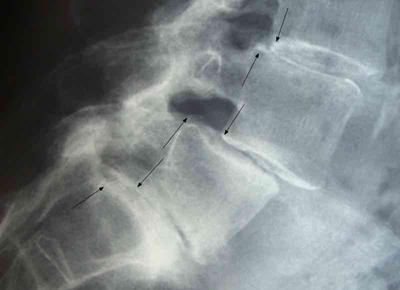

Spondylolysthesis

Last year I had rods and screws inserted to relieve a spondyolysthesis at L3/4, but the pain and cramps that I am getting in both my legs, although much worse on the right, is much worse than before the op.